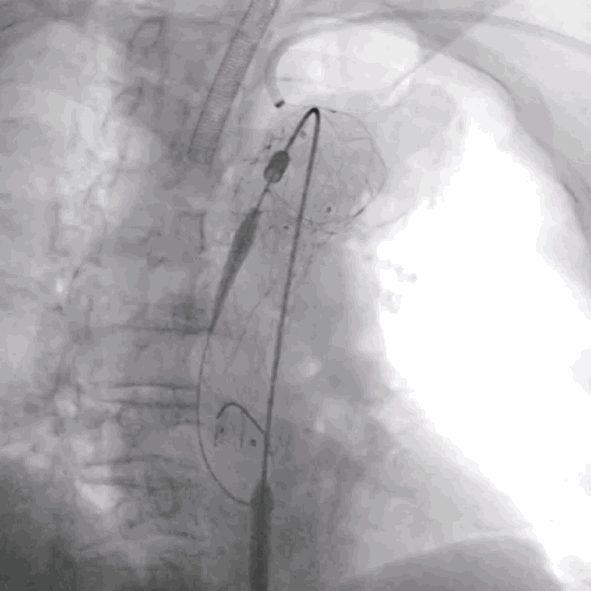

3. 沿左侧肱动脉Fustar内导入Fusmart可调弯导管及0.035"Terumo普通泥鳅导丝尾端,到达主动脉弓覆膜支架上方,调整角度,以尽量垂直角度透视下配合破膜,选入主体支架内,LSA导管内造影,多角度确认导丝头穿过主动脉支架覆膜。

LSA可调弯鞘内进可调弯导管

RAO方向确认导管

与大支架覆膜垂直

破膜成功

LSA导管内造影,确认破膜成功